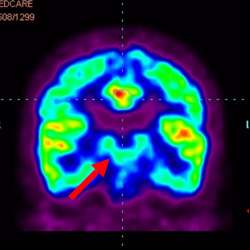

干細(xì)胞治療腦癱后改善的客觀放射學(xué)證據(jù)

細(xì)胞治療后,藍(lán)色和黑色區(qū)域減少,并且看到更活躍的區(qū)域。這表明損傷減少并改善了大腦功能。

細(xì)胞治療前 PET CT 掃描顯示神經(jīng)組織中的藍(lán)/黑色區(qū)域,表明腦癱引起的大腦損傷。

這證明細(xì)胞療法是治療腦癱兒童安全有效的方法。細(xì)胞療法可以更新大腦損傷的核心,并且可以通過 PET CT 掃描來監(jiān)測(cè)大腦的改善情況。這些細(xì)胞療法與標(biāo)準(zhǔn)治療一起促進(jìn)腦癱兒童的生長(zhǎng)和改善。